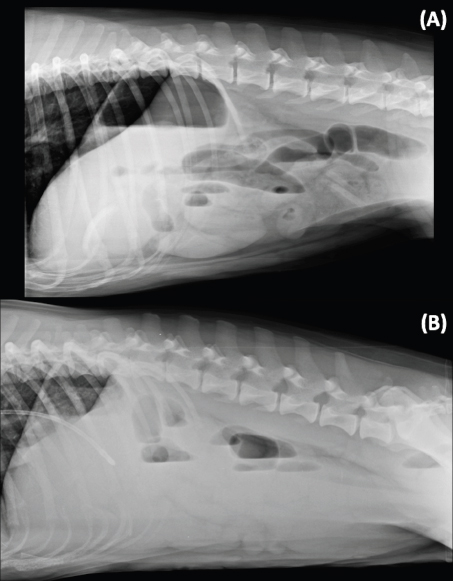

The presence of variable gas-capped fluid lines has been reported as a radiographic sign of mechanical gastrointestinal ileus in the HB view (Gibbs and Pearson, 1973; Harlow et al., 1993). This study confirms that 78.8% of the mechanical ileus cases exhibit this sign. However, this is not specific as 30.3% of the without mechanical ileus cases also have this similar radiographic sign (Fig. 2). Thus, the presence of gas-capped fluid lines in the HB view needs to be interpreted carefully and it is not a pathognomonic sign for mechanical ileus. However, it may suggest mechanical ileus and need further investigation.

Fig. 2. Left-to-right lateral HB views in sternal recumbency of two different patients. (A) A dog with mechanical ileus due to a gastro-jejunal linear foreign body. Note the presence of different levels of the gas-capped fluid lines in the small intestine. Additionally, there is a curvilinear radiopaque structure in the stomach, which was not identified in the standard VB views but recognized on the HB view. (B) A dog diagnosed with gastrointestinal intoxication secondary to mushroom ingestion in group P. Note the presence of the different level of gas-capped fluid lines in the small intestines’ loops.